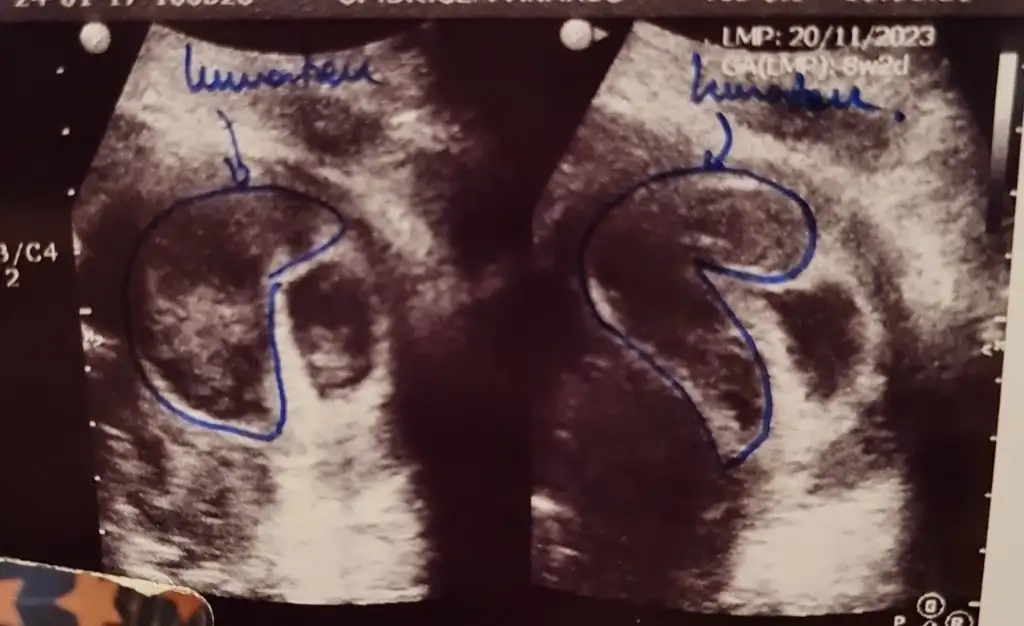

arkadaslar bebegimi ilk gormeye gittigimizde 5+4 tu yolk kesesini gorduk ve gayet iyiydi hersey smdi 7+2 de hem bebisimi hemde kalp atisini gormeye gitcektik 7+1 birgun once gece ani bi kanamayla acile gittik kanamam adet gibi yogundu ve asiri buyuk ciger gibi kan pihtilari dustu ertesi gun doktorumla randovumuz vardi zaten gittik bebisin kalp atisini duyduk bebekte iyiydi kesede zarar gormemisti ama kanama alanima acildeki doktorda kendi doktorumda cok buyuk dedi 4.2 cmye 1.35 cm cikti benim bebegim tup bebek gunde 3 kere yumurta toplamadan beri fitil seklinde progestan 200 kullaniyodum smdi + olarak progestan dex igne verdi gunde 1 adet doktorumun dedigi dinlenmem agir is yapmamam bebek eger saglikliyla bisey olmicagini soyledi hatta kanin akmasi hastalari korkutsada onu memnun ediyomus basinc olusturmuyomus boylelikle icerde bebek buyudukce rahimde daha fazla yer kaplamaya basladikca kanama dururmus bu boyutlarda bi kanama yasayan var mi yada boyle bi kanama yasayip sonrasi ne oldu kanama alaninin gorselini ekliyorum tarali alan

benim dun kontrolum vardi kanama alanimiz daha cok buyumus alanimiz onceden 4 x 1.3 cm di simdi 5 x 4 kusur dedi ama bebis gayet iyi benim doktorum kanin akmasini istiyoki birikmesin iceride basinc yapmasin diye birde akarsa daha hizli bosalir vucudun emmesini beklersek daha gec biter diyo o yuzden bence sizde korkmayin sizin cmleriniz nasil ben eski ve gunceli koyuyim tekrar ama bu kontrolde karindan baktigi icin sol saga dondu aynalama oldu yani siz tukenmezle cizili olan resmi kan alani sagda dusunun lutfen